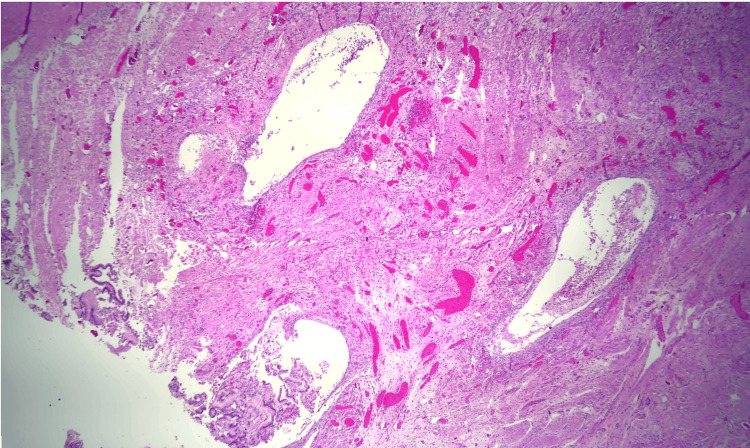

Due to the patient’s symptoms, risk factors, and degree of obstruction, these findings were concerning for possible metastasis. Both gastroenterology and general surgery were consulted for consideration of either endoscopic ultrasound with fine-needle aspiration or open surgical biopsy of the mass. Ultimately after multidisciplinary discussion, general surgery was planned for a biopsy of the mass and management with PD. Pathology revealed Brunner gland hyperplasia, pseudocysts with granulation tissue, chronic inflammation, and proteinaceous material consistent with GP (Figures 6–8). MRI of the liver deemed the lesion to be a benign hemangioma. Additionally, cluster of differentiation 31 (CD31), human herpesvirus-8 (HHV-8), and Helicobacter pylori immunostaining were all negative. He did well postoperatively and was discharged with bilateral Jackson-Pratt drains. At his outpatient follow-up, he endorsed improvement in appetite and resolution of his symptoms.